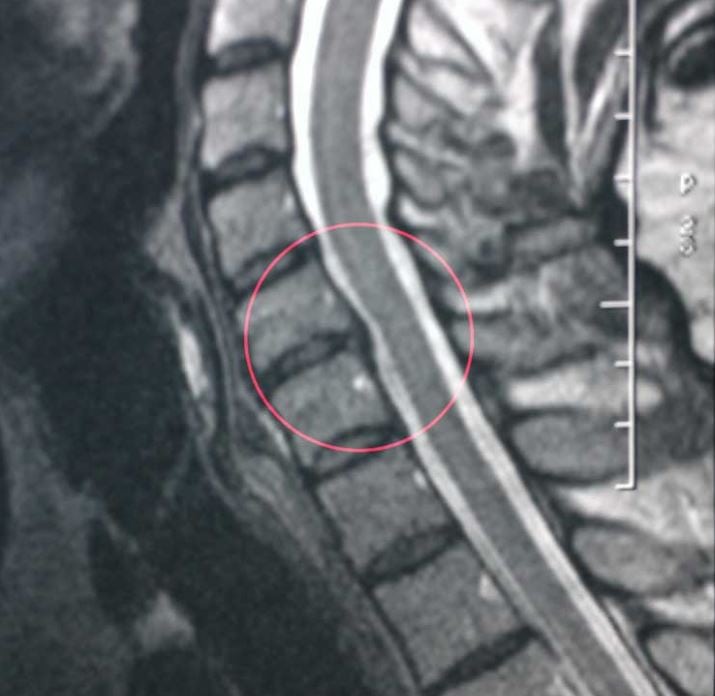

Связано это с дегенеративными изменениями хрящевого диска. Кровеносные сосуды шейного отдела позвоночника защемляются, что нарушает кровообращение. Головной мозг страдает из-за недостаточного снабжения кислородом, и слух обостряется, улавливая тот шум, который не должен. А исходит он от нервных клеток, лишенных «мозговых сигналов». Издавая собственные непрерывные сигналы, они заполняют этот пробел.